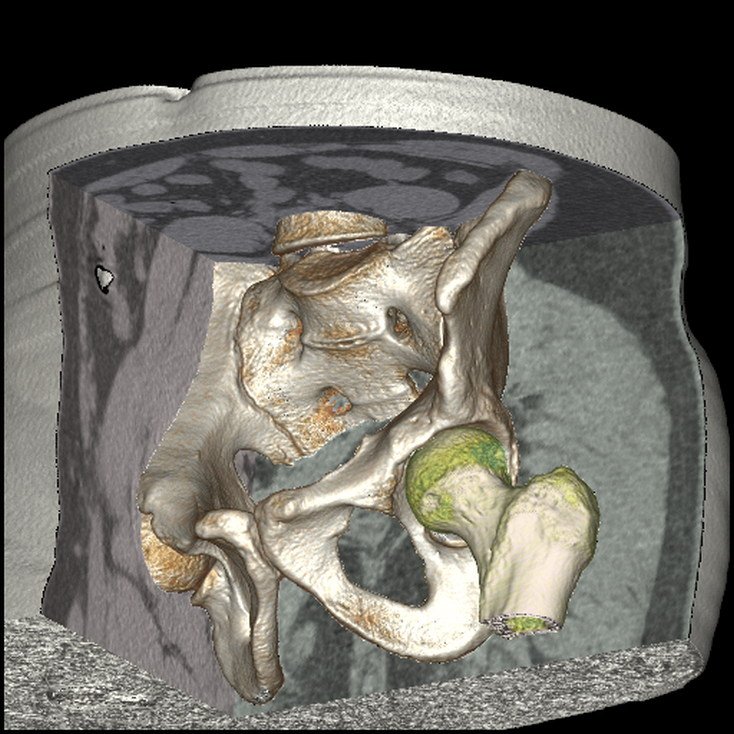

3D CT Hip

3D CT Pelvis